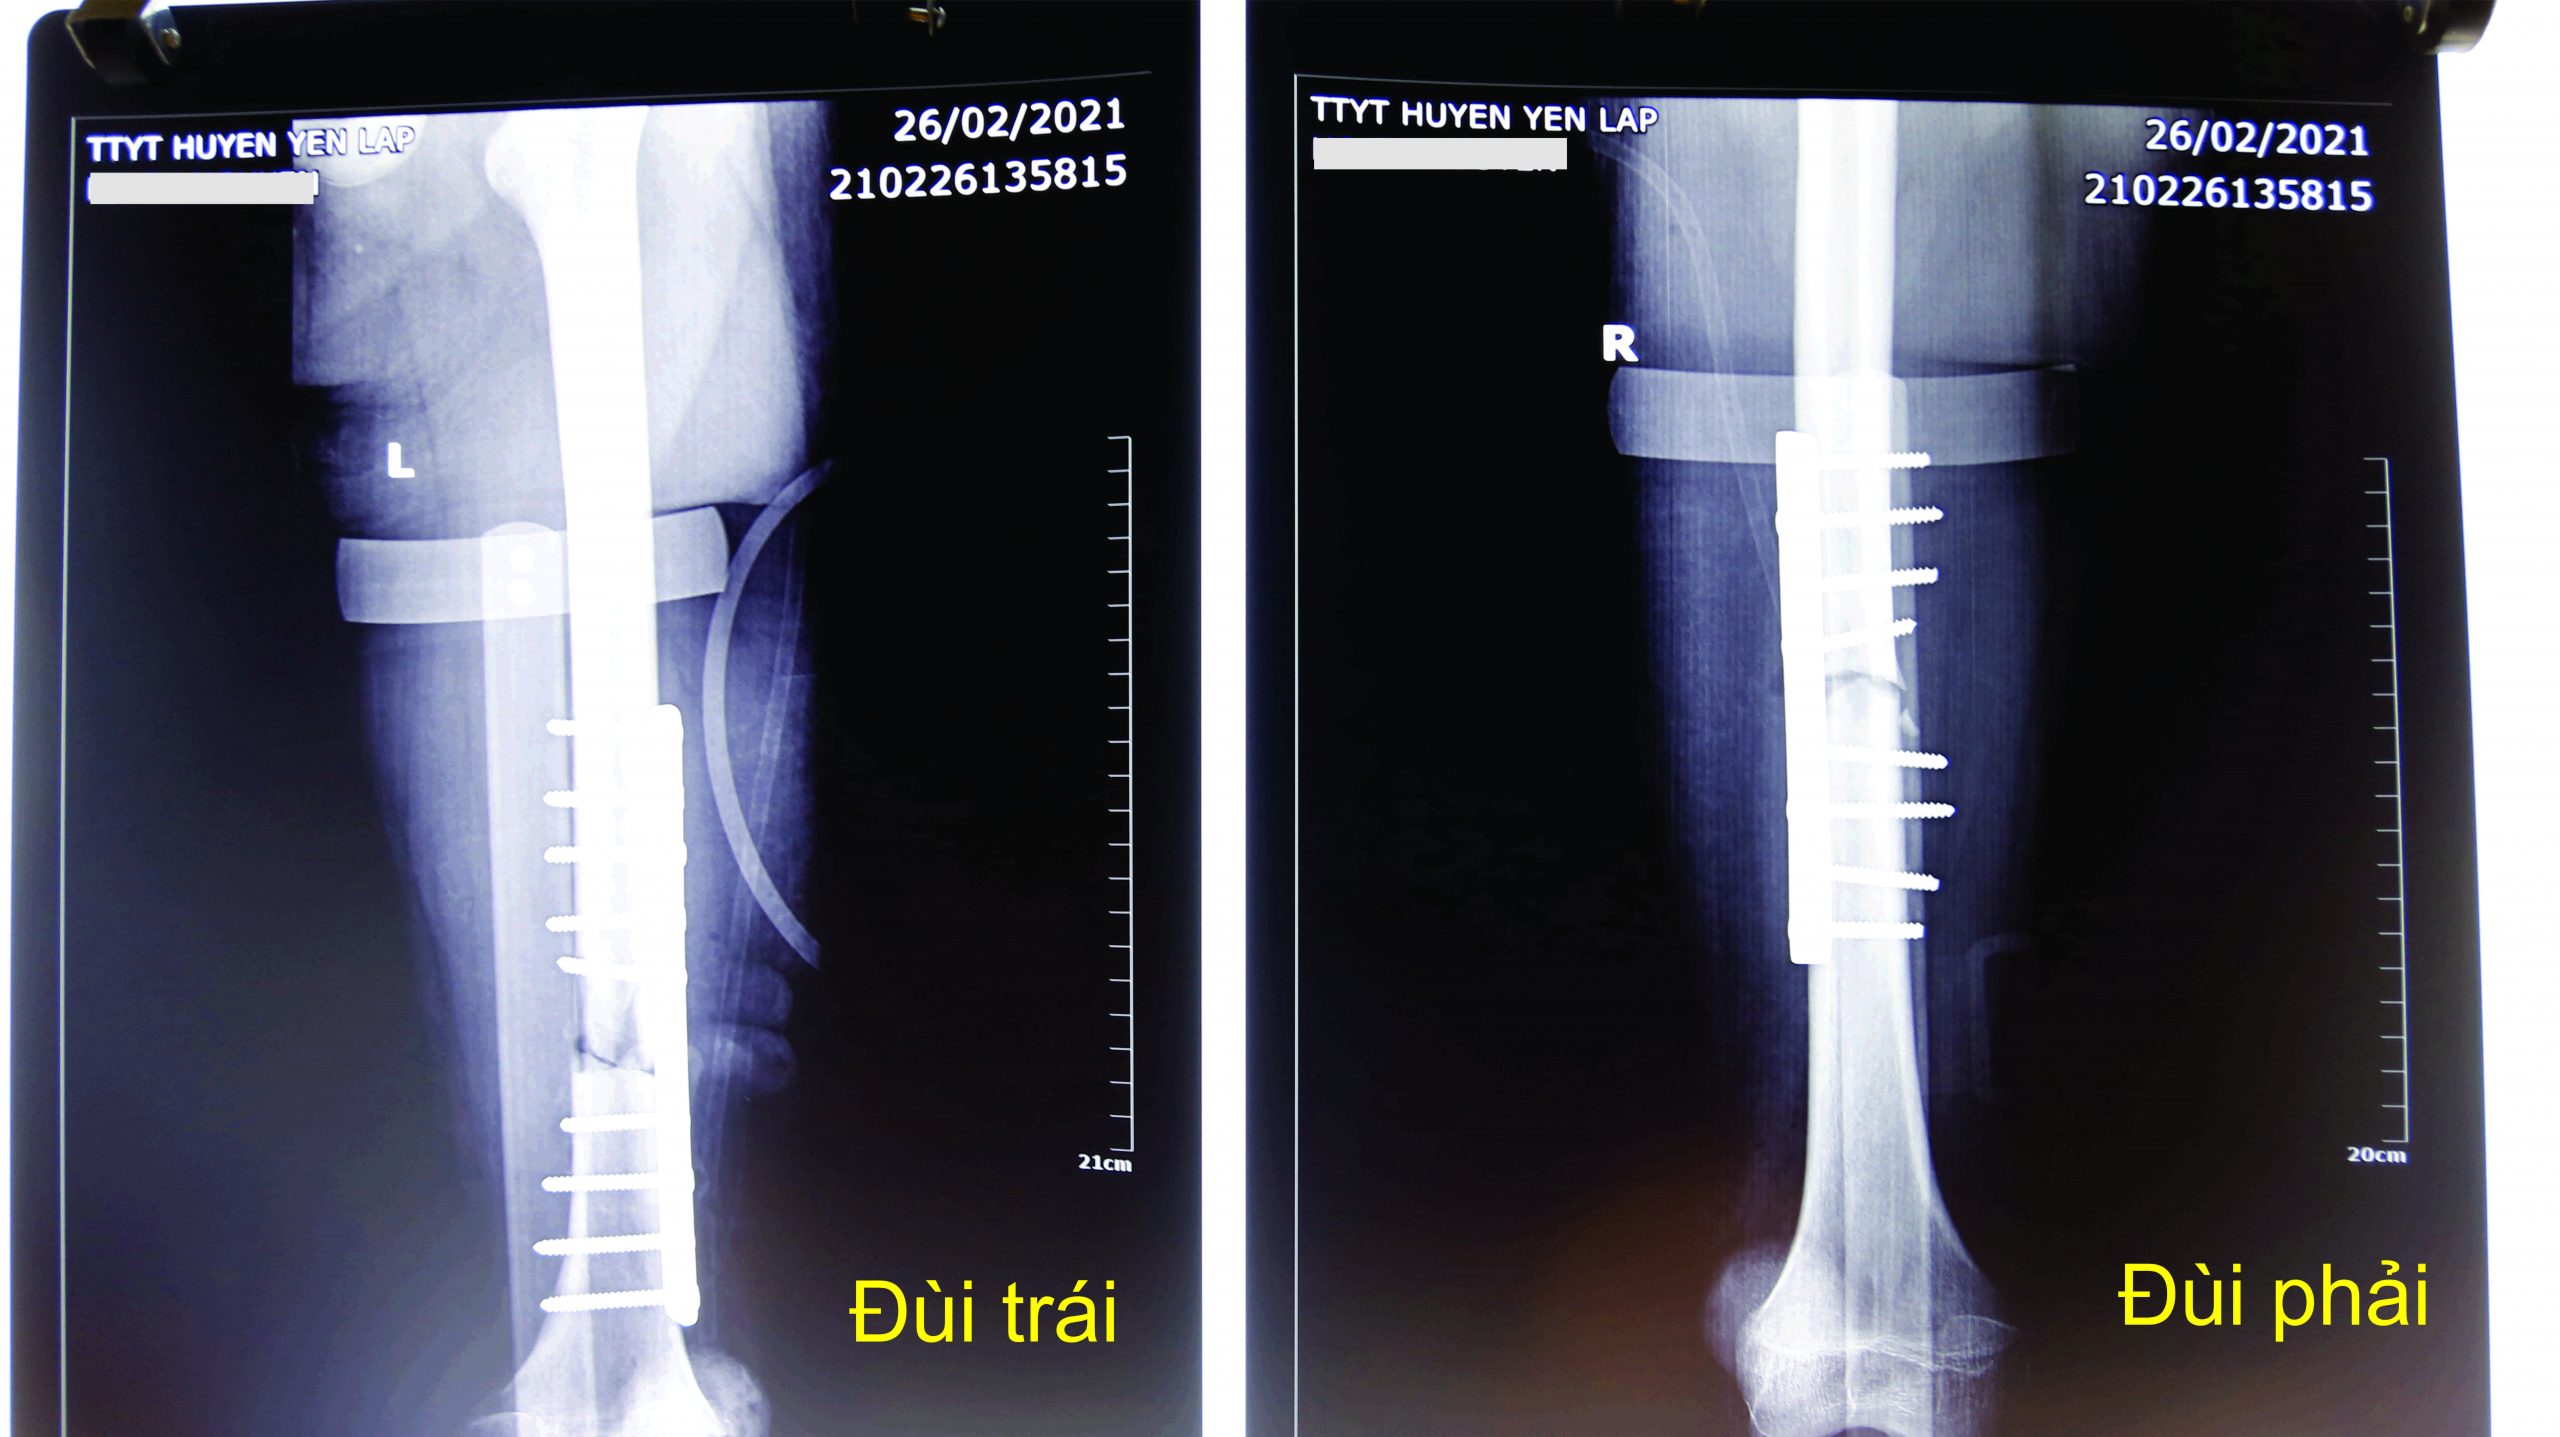

Do xương đùi bên trái bệnh nhân bị gãy hở, để ngăn ngừa nhiễm trùng, ngay lập tức các bác sĩ tiến hành hội chẩn gấp và chỉ định phẫu thuật cho bệnh nhân. Kíp Phẫu thuật do bác sỹ chuyên khoa I Hoàng Mạnh Thuần, Phó Trưởng khoa Ngoại Tổng hợp – Chuyên khoa làm trưởng kíp đã tiến hành phẫu thuật kết hợp xương đùi bằng phương pháp nẹp vít (Xương đùi là 1 xương dài nhất cơ thể, có nhiều cơ xung quanh nên khi gãy xương đùi, thường không điều trị bảo tồn được mà phải phẫu thuật kết hợp xương).

Quá trình thực hiện phẫu thuật các bác sỹ tiến hành cắt lọc vết thương bên đùi trái, loại bỏ phần da, cơ bị dập và những mảnh xương nhỏ. Dùng kìm cặp hai đầu xương gãy, làm sạch hai đầu xương gãy và đặt hai đầu xương gãy về đúng vị trí. Sau đó sử dụng khoan để bắt vít vào nẹp nhằm cố định hai đầu xương gãy. Đối với phần đùi phải của bệnh nhân, các bác sỹ tiến hành rạch da theo đường định hướng từ mấu chuyển lớn đến lồi cầu ngoài xương đùi. Bóc tách cơ vào xương theo vách gian cơ ngoài, rồi tiếp tục thực hiện các bước cố định xương. Ca phẫu thuật kéo dài hơn 3 tiếng, từ 11h đến 14h20’h.

Bệnh nhân được truyền 02 đơn vị máu nhóm B. Hai chân sử dụng tổng cộng 18 vít xương và 2 nẹp bản rộng.